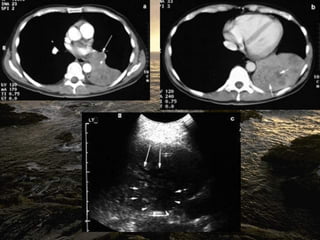

Notice the increased lucency of the cardiophrenic sulci in this patient

with inferior anteromedial pneumothoraces. A CT scan confirms the

diagnosis

Notice the increasedlucency of the cardiophrenic sulci in this patient with inferior anteromedial pneumothoraces. A CT scan confirms the diagnosis

• 44.

 a hyperlucentupper quadrant with visualization of the superior surface of the diaphragm and visualization of the inferiorvena cava.  double-diaphragm sign

• 45.

 Antero lateralair may increase the radiolucency at the costo phrenicsulcus. This is called the deep sulcus sign.